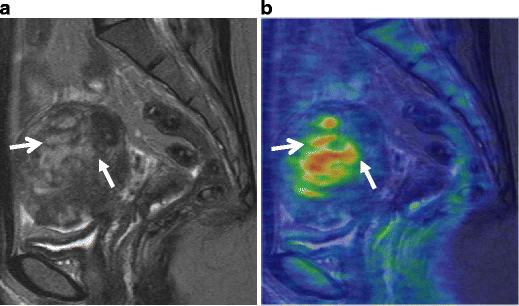

Endometrioid carcinoma in 69-year-old woman. a T2-weighted image demonstrates an ill-defined myometrial mass of decreased intensity (arrows). b Fusion image with DWI onto T2-weighted image shows increased intensity in the myometrial mass, which represents endometrioid carcinoma infiltrating into the myometrium